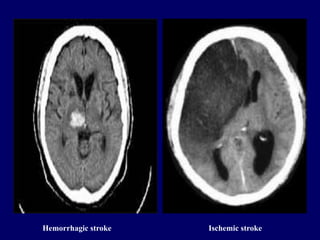

IMAGING

1. Computerized Tomography

-Commonly used imaging technique

-Allows identification of large arteries

and vein, and venous sinuses

-Used to rule out other brain lesions

Hemorrhagic stroke Ischemic stroke